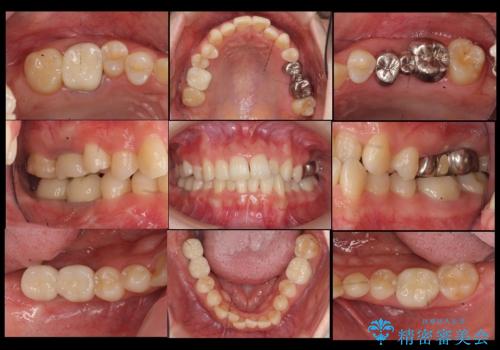

右上に部分矯正を行い、クリアランスを確保した後、右下にイプラントを2本埋入しています。

- およそ150万円 部分矯正30万円、インプラント治療37万円×2本、右上7emaxインレー、右上6 専門医による再根管治療およびジルコニアクラウン26万円費用は治療当時の料金となります

上の歯が伸びだしてきていたため、部分矯正を行い歯を移動させてから、向かい合わせの歯にインプラント治療を行っています。

右上第一大臼歯は六本木院の林院長に根管治療をお願いしました。